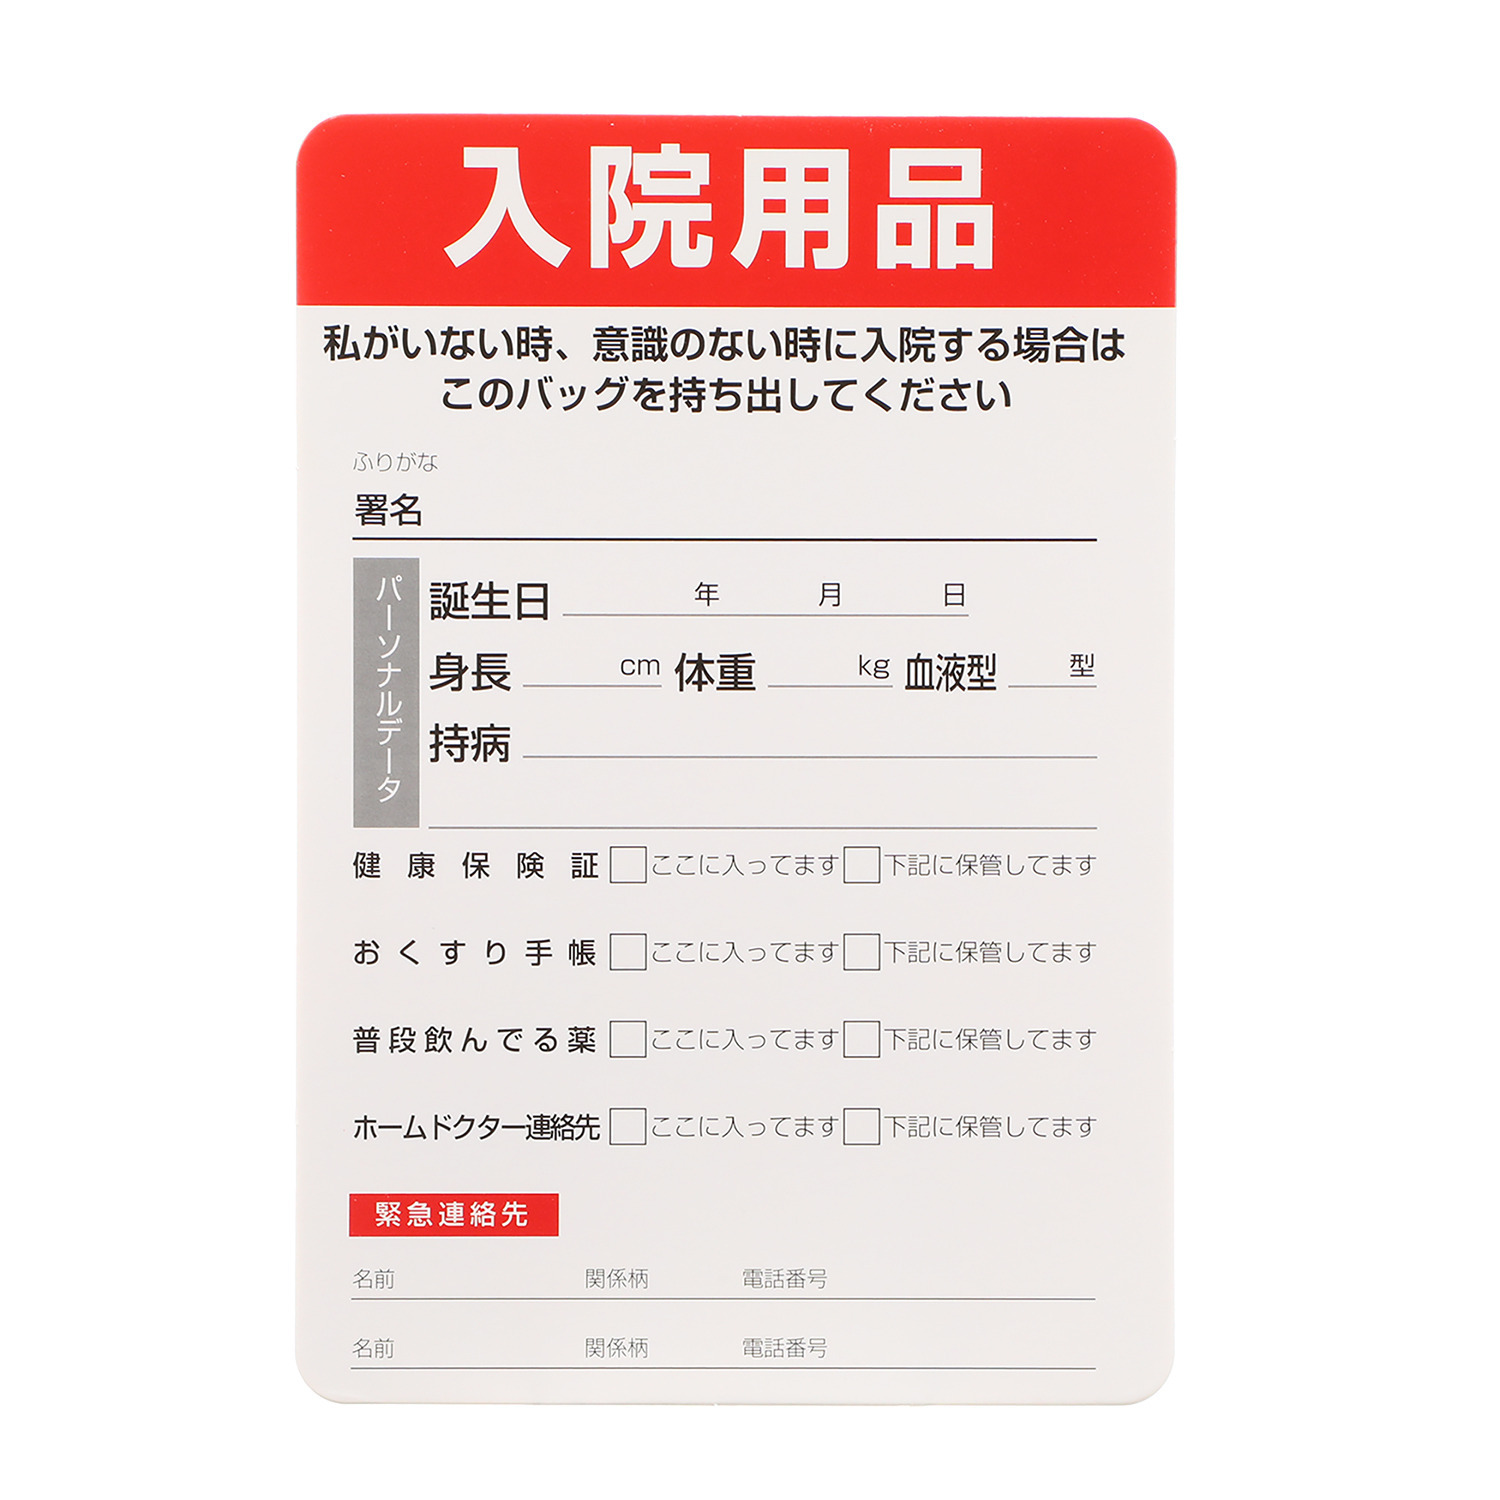

付属の「入院用品カード」にはご自身のパーソナルデータや緊急連絡先などを記入でき、さらに「入院用品カード」を外側ポケットに入れておくことで、押し入れなどに収納していても見つけやすくなっています。

【付属品】

・底板、入院用品カード